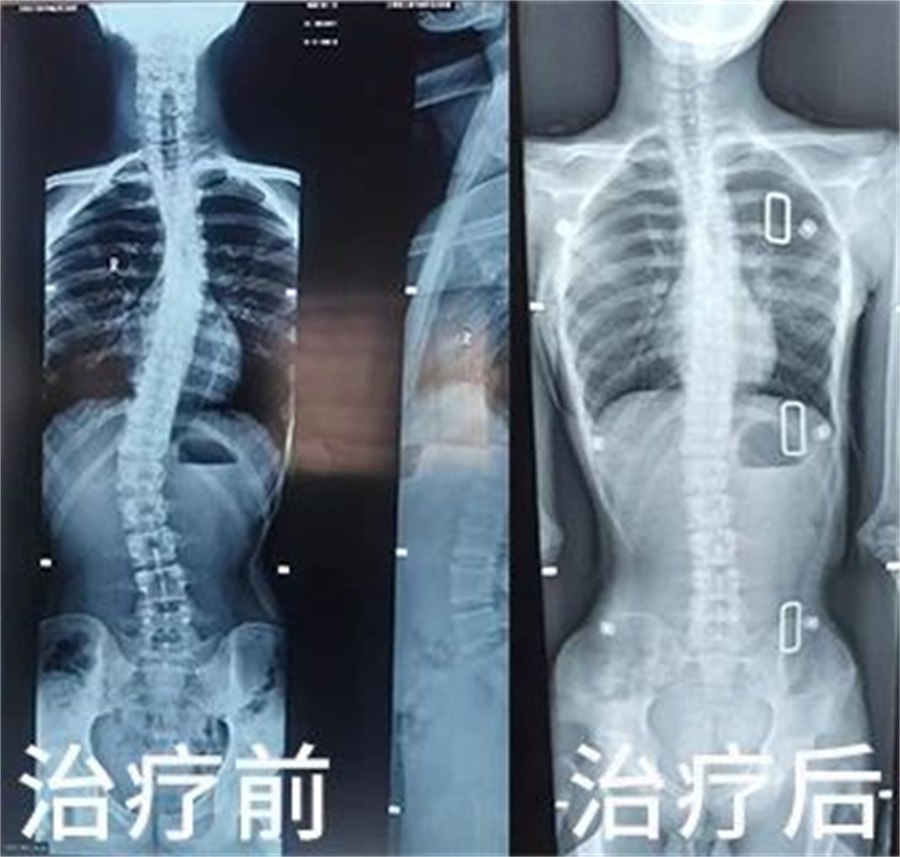

10度以下的小幅度脊柱侧弯比较常见,家长不必过于焦虑。如果侧弯大于20度,或者每年进展超过5度,但是在临床上没有合并神经肌肉疾病、没有半椎体骨骼畸形等情况,一般会采取支具固定等保守治疗,同时进行功能锻炼。如果脊柱侧弯大于45度,或者脊柱已经没有生长空间,则需要手术治疗。